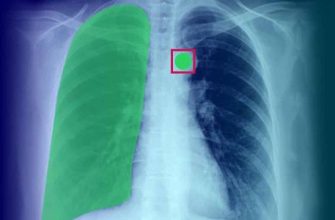

Автоматизация и Оптимизация DICOM: От пикселя к диагнозу – Как мы разрабатываем